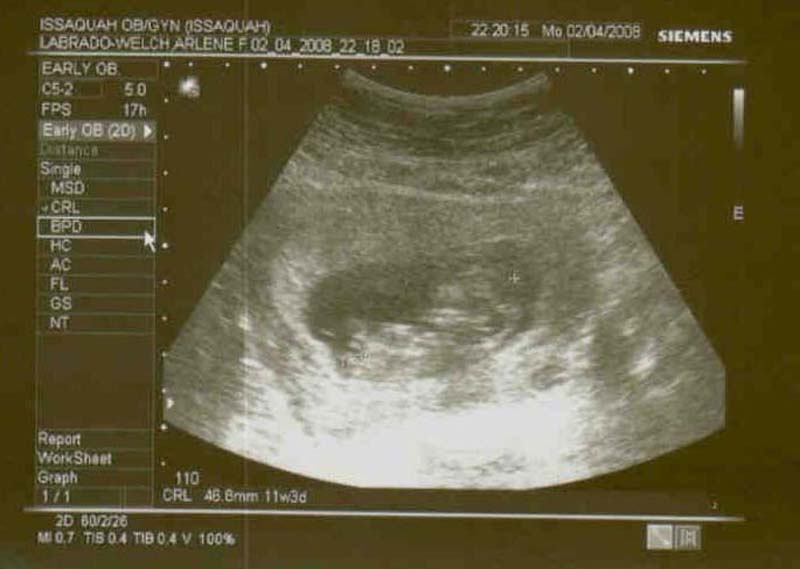

Baby Welch 11 weeks